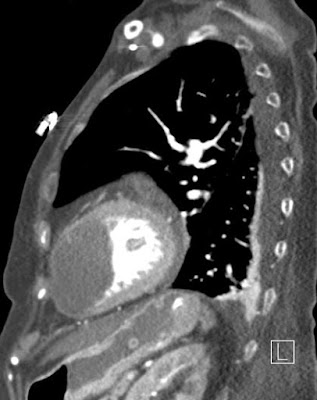

Szerző: admin | júl 6, 2011 | Cardial, PE, Thrombosis

Kamrai infarctust követően kialakult szívcsúcsi aneurysma talaján fejlődött thrombusmelléklelet: thromboembólus a jobb alsó lebenyt ellátó pulmonalis törzsben7802762011.07.06.